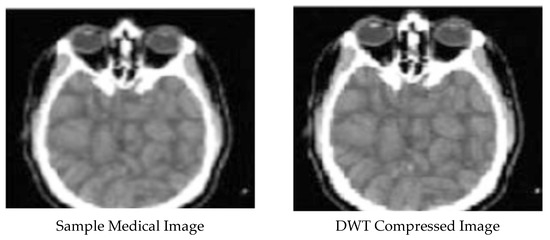

Enhanced and Compressed Output

| 1 | DCT compressed Image | 0.976102286 | 4.15 × 10−5 | 89.97979612 |

| 3 | DWT compressed image | 0.060732271 | 0.555070285 | 54.76541543 |